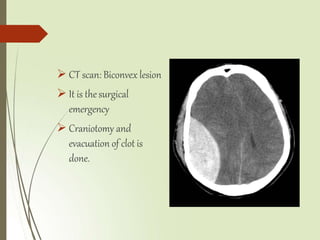

 CT scan: Biconvex lesion

 It is thesurgical

emergency

 Craniotomy and

evacuation of clot is

done.